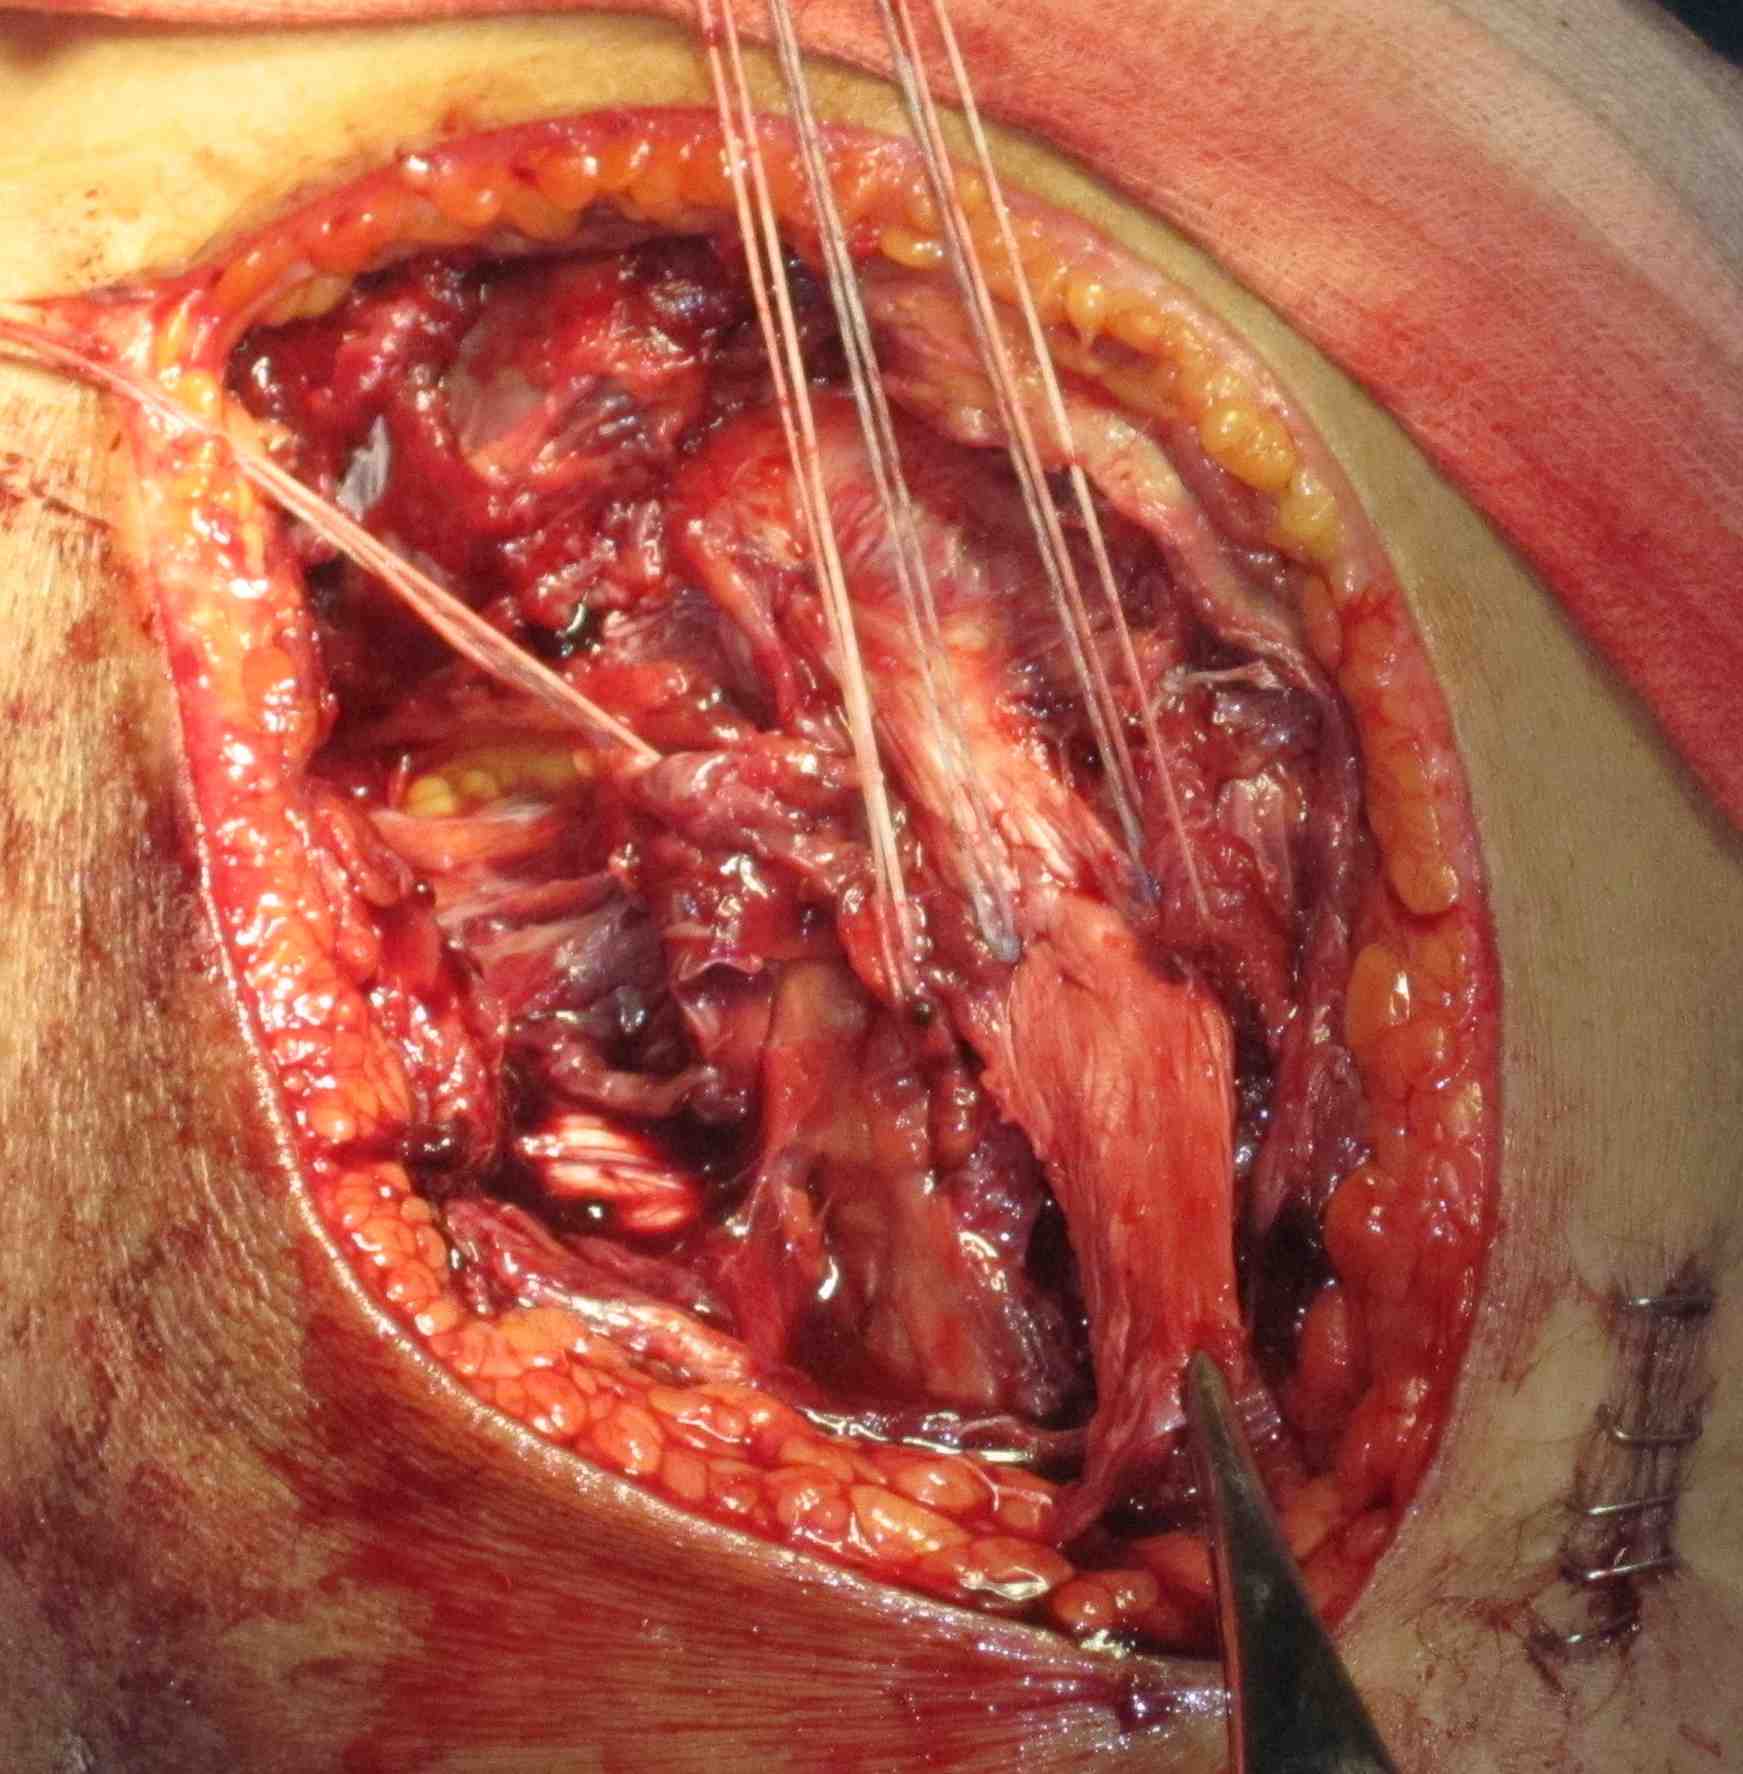

MCL repair

Tibial side

Femoral side

Hughston Procedure

- advance femoral attachment of MCL and POL

- tighten POL anteriorly onto MCL

- consider imbricating semimembranosus to decrease slack

Advancement of proximal MCL / POL with screw, and imbrication / tightening of POL

Tightening of proximal MCL / POL with sutures

Advancement of femoral MCL and staple / suture anchor fixation